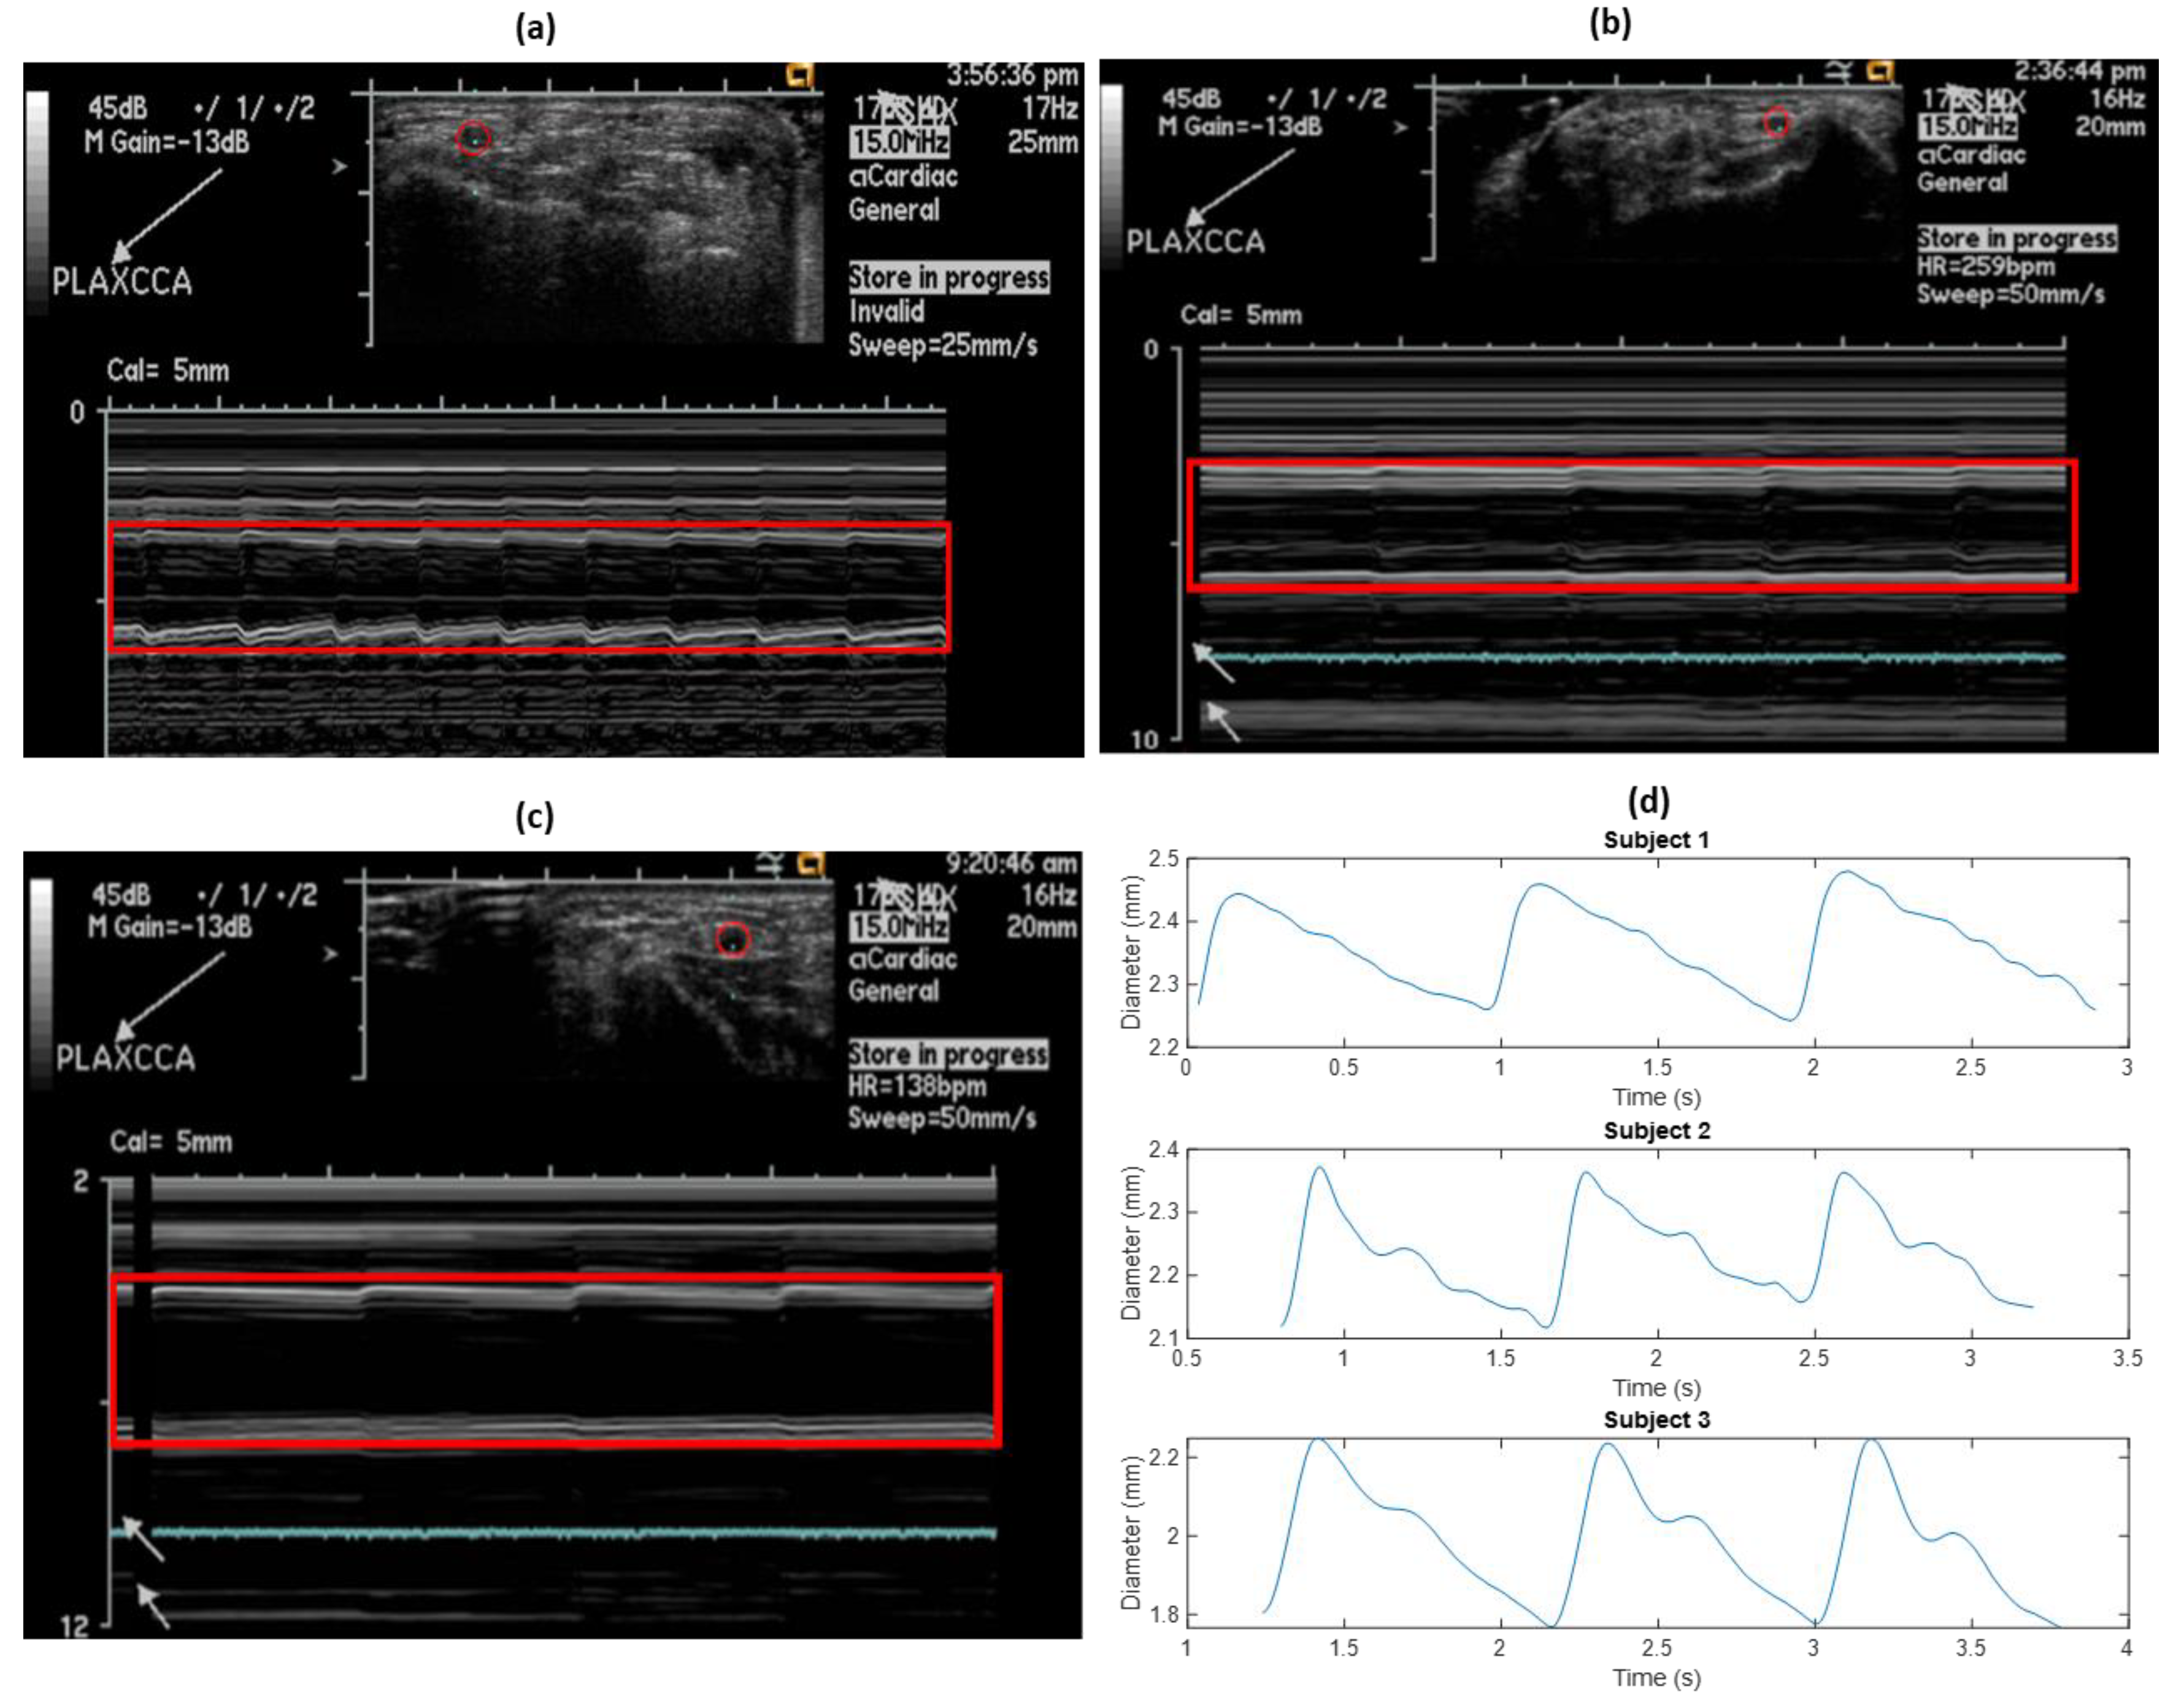

As a reference, ultrasound measurements to estimate the diameter of the left radial artery were performed on all three subjects, at the same time as the impedance measurements. Initially, the probe was adjusted to correctly locate the cross-section of the artery for M-mode analysis. Figure 5a–c show the cross-sectional diameter changes in the left radial artery for all the three subjects, as captured from the ultrasound.

Extraction of the diameter waveform was performed using image processing in MATLAB. Each ultrasound image was smoothened, and contours were extracted containing the information of each related pixel. The contours for the near- and far-artery walls (on the probe) were identified, and the overall diameter waveform was obtained as a difference between the two. The extracted diameter waveform from the above ultrasound images for all the subjects can be seen in Figure 5b.

Figure 5. (ac) Radial artery diameter changes measured using ultrasound for subjects 1, 2 and 3, respectively. The artery is outlined by a red circle and the corresponding M-mode diameter wave is outlined using a red rectangle. (d) Extracted diameter waveforms for the subjects from ultrasound measurements.